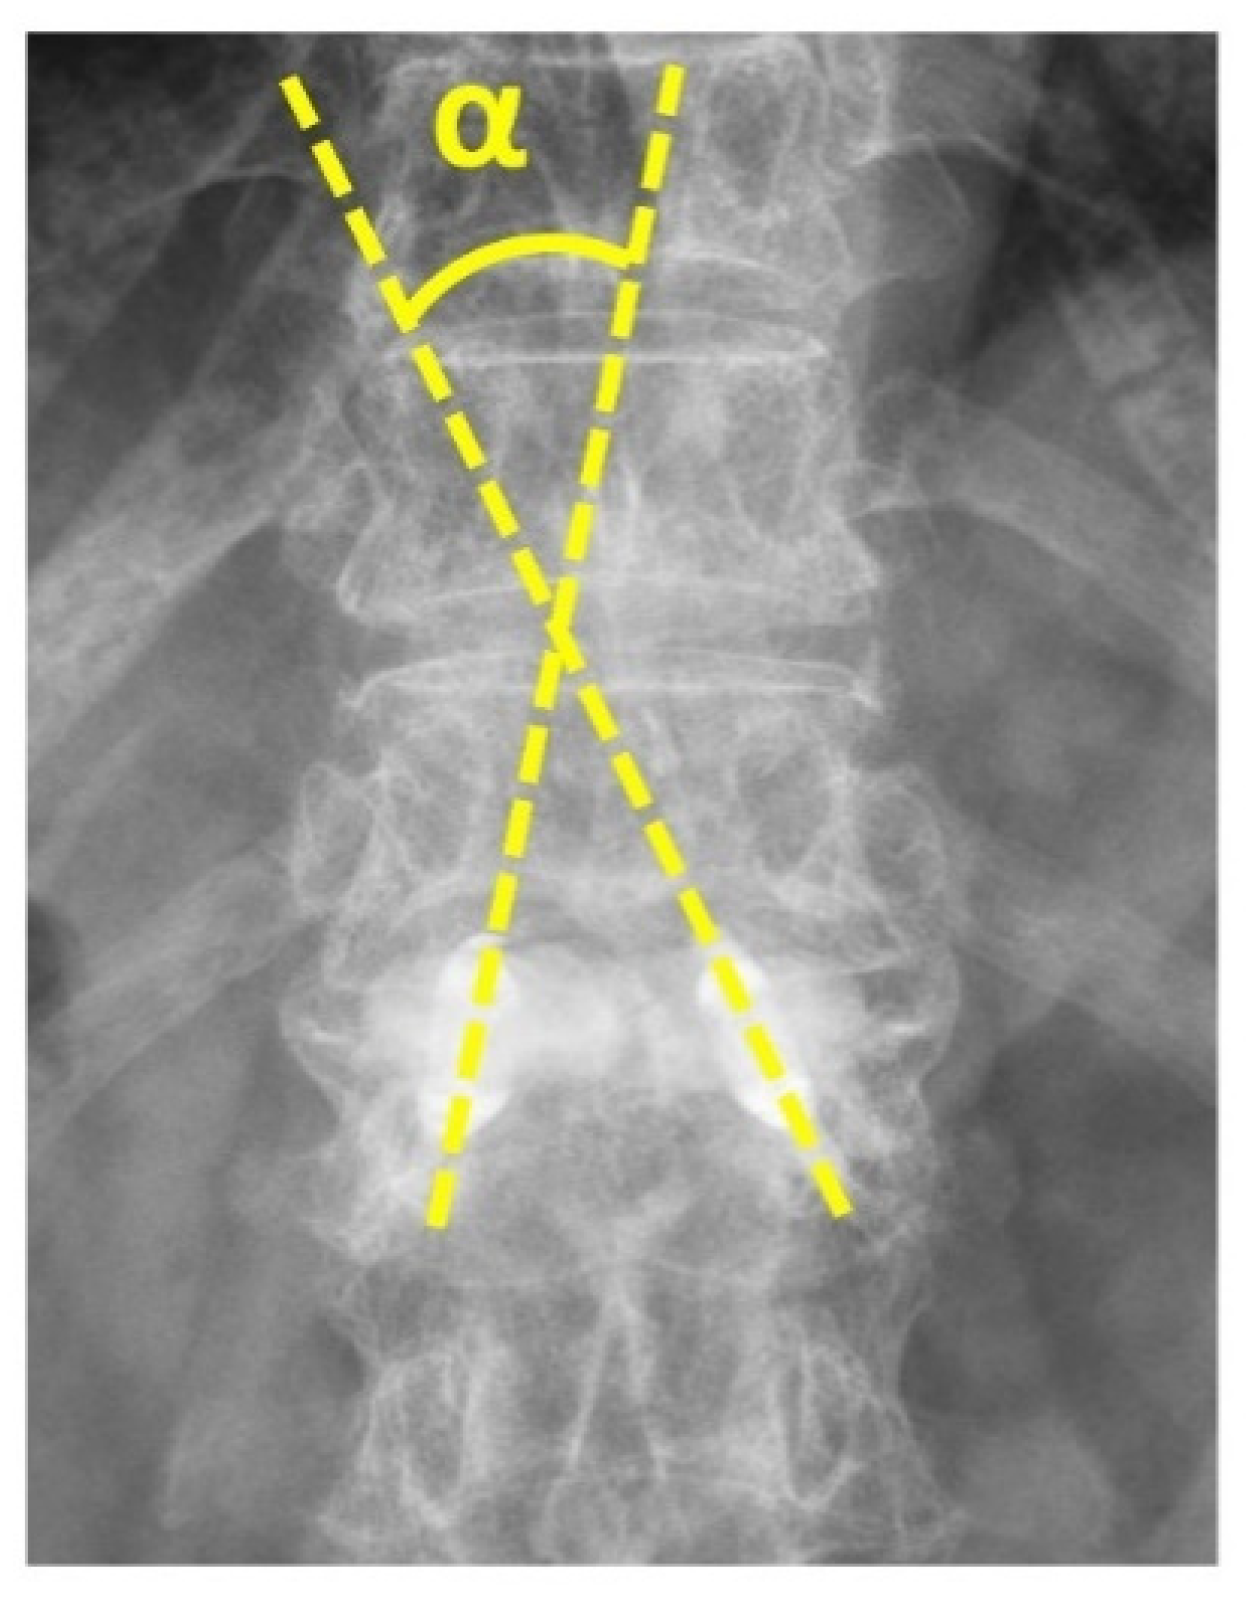

“Double Cross Sign” Could Be an Indicator of an Adequate Amount of Bone Cement in Kyphoplasty with the SpineJack System: A Retrospective Study

| Δ regional kyphotic angle (degrees) | 11 ± 8.8 | 5.3 ± 3.2 | p = 0.001 * |

| Δ local kyphotic angle (degrees) | 11.7 ± 6.2 | 6.6 ± 4.1 | p = 0.001 * |

| Angle change between devices (mL) | 3.7 ± 4.3 | 9 ± 4.7 | p = 0.002 * |